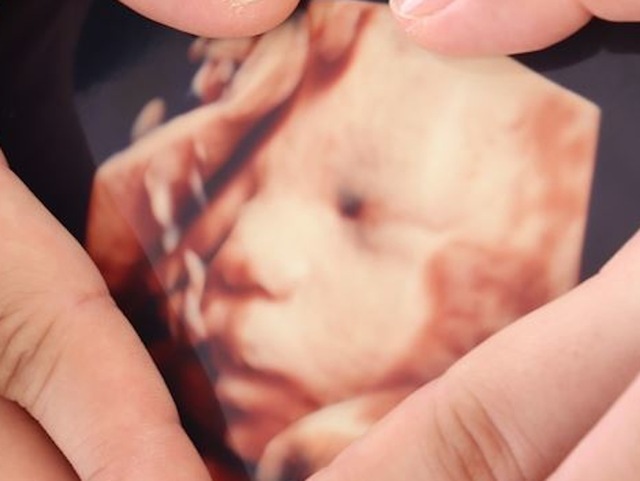

34週0日(34w0d・女の子)|えりか413 さん(27歳)

エコー写真撮影時のエピソード:

ず~っと顔を見せてくれなくて、いつも手が邪魔していたり、へその緒や胎盤で見えなかったのですが、エコーで唯一お顔を見せてくれた一枚です。 お兄ちゃん達と同じ顔で、生まれてくる子もまた似てるのかな~なんて夫婦で盛り上がりました♡